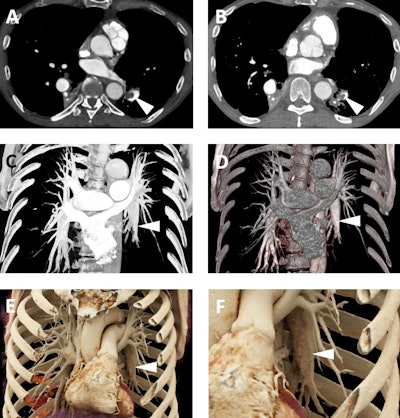

Cinematic rendering also better visualizes chronic pulmonary embolism than does traditional volume rendering, possibly as a result of its capacity to discern the subtle textural difference associated with eccentric clots on the vessel wall, as demonstrated in the figure below.

A 65-year-old man with a history of chronic thromboembolic disease. A and B: Axial postcontrast 2D CT images demonstrating eccentric filling defects in dilated left lower lobe pulmonary arterial branches (white arrowheads) compatible with chronic pulmonary embolism. C and D: Volume-rendered images demonstrate the dilated lower lobe pulmonary arteries (white arrowheads), although the eccentric filling defects from the clots are not well seen on these images. E and F: Cinematic rendering images (F is a blown up detail from E) again show the dilated lower lobe pulmonary arteries (white arrowheads), but due to the higher detail of cinematic rendering, there is a subtle textural change in the left lower lobar pulmonary artery (best seen in F) that is consistent with the patient's chronic pulmonary embolism.